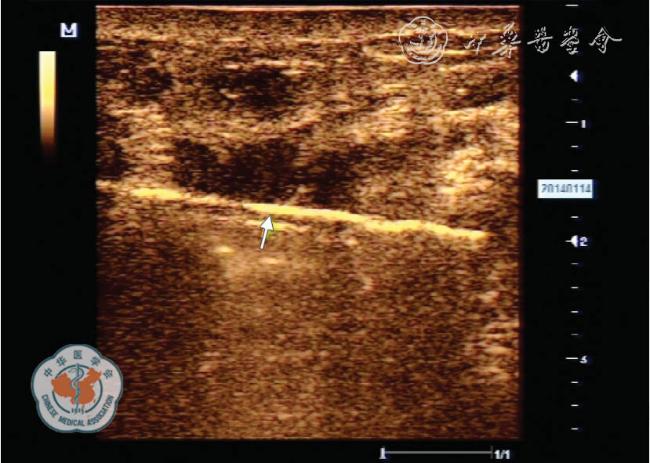

图4 超声引导下麦默通乳腺微创旋切术清除聚丙烯酰胺凝胶(PAHG)

在超声引导下可准确切除移位至腺体内且小于1 cm 的PAHG;如图所示,旋切刀头端凹槽完全对准PAHG 进行旋切

麦默通乳腺微创旋切术在注射式隆乳材料取出中的应用,目前鲜见文献报道。 本科于2009 年2 月至2013 年4 月对38 例PAHG 隆乳患者利用麦默通微创旋切技术行隆乳材料取出,收到了良好的效果。 笔者认为该术式对注射式隆乳材料取出的适应证包括:(1)惧怕PAHG 毒性及其不良反应者;(2)注射PAHG 发生游走移位,特别是对于移位至腺体内且小于1 cm 的PAHG,利用该术式可准确切除(图4);(3)注射PAHG 后继发感染,可通过该术式清除PAHG、脓液及炎性病变组织,并可通过留置负压引流管以便术后反复冲洗创腔。